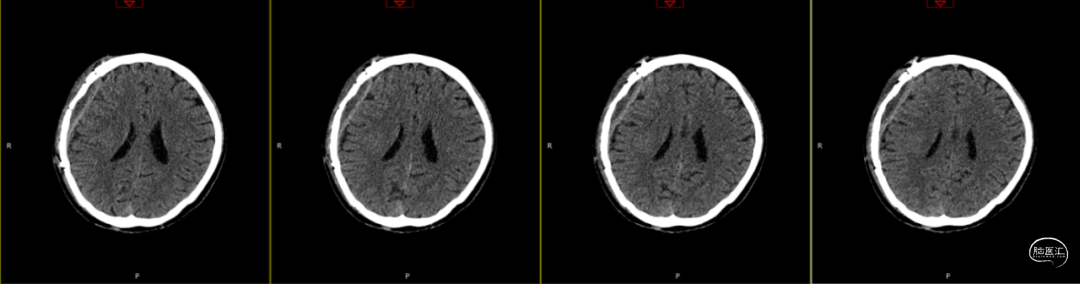

查体:嗜睡-昏睡状态,精神差,刺激睁眼,简单应答,肢体活动简单从嘱。GCS13分。双侧瞳孔等大等圆,直径2.5mm,对光反射灵敏,伸舌欠合作。转头、耸肩欠合作,四肢肌力4级,肌张力正常,颈抵抗(+),双Babinski sign未引出。枕部可见约5*4cm皮下血肿,压痛,拒按。周身多发片状皮肤擦伤。颅脑CT:双侧额叶脑挫裂伤;右侧顶颞枕部硬膜外、硬膜下血肿;蛛网膜下腔出血;右侧颞骨骨折累及右侧人字缝、顶乳缝,右侧顶乳缝旁小骨片;头皮软组织损伤、局部皮下血肿;双肺挫伤可能。

因患者在病情观察期间意识状态变差,昏睡-浅昏迷状态,予以急症手术治疗,清除硬膜外血肿,鉴于术中脑组织压力不高,予以骨瓣回置,术后严格控制血糖水平,常规使用抗生素(头孢唑林钠)预防感染。

术后第1天颅脑CT复查(如上图)